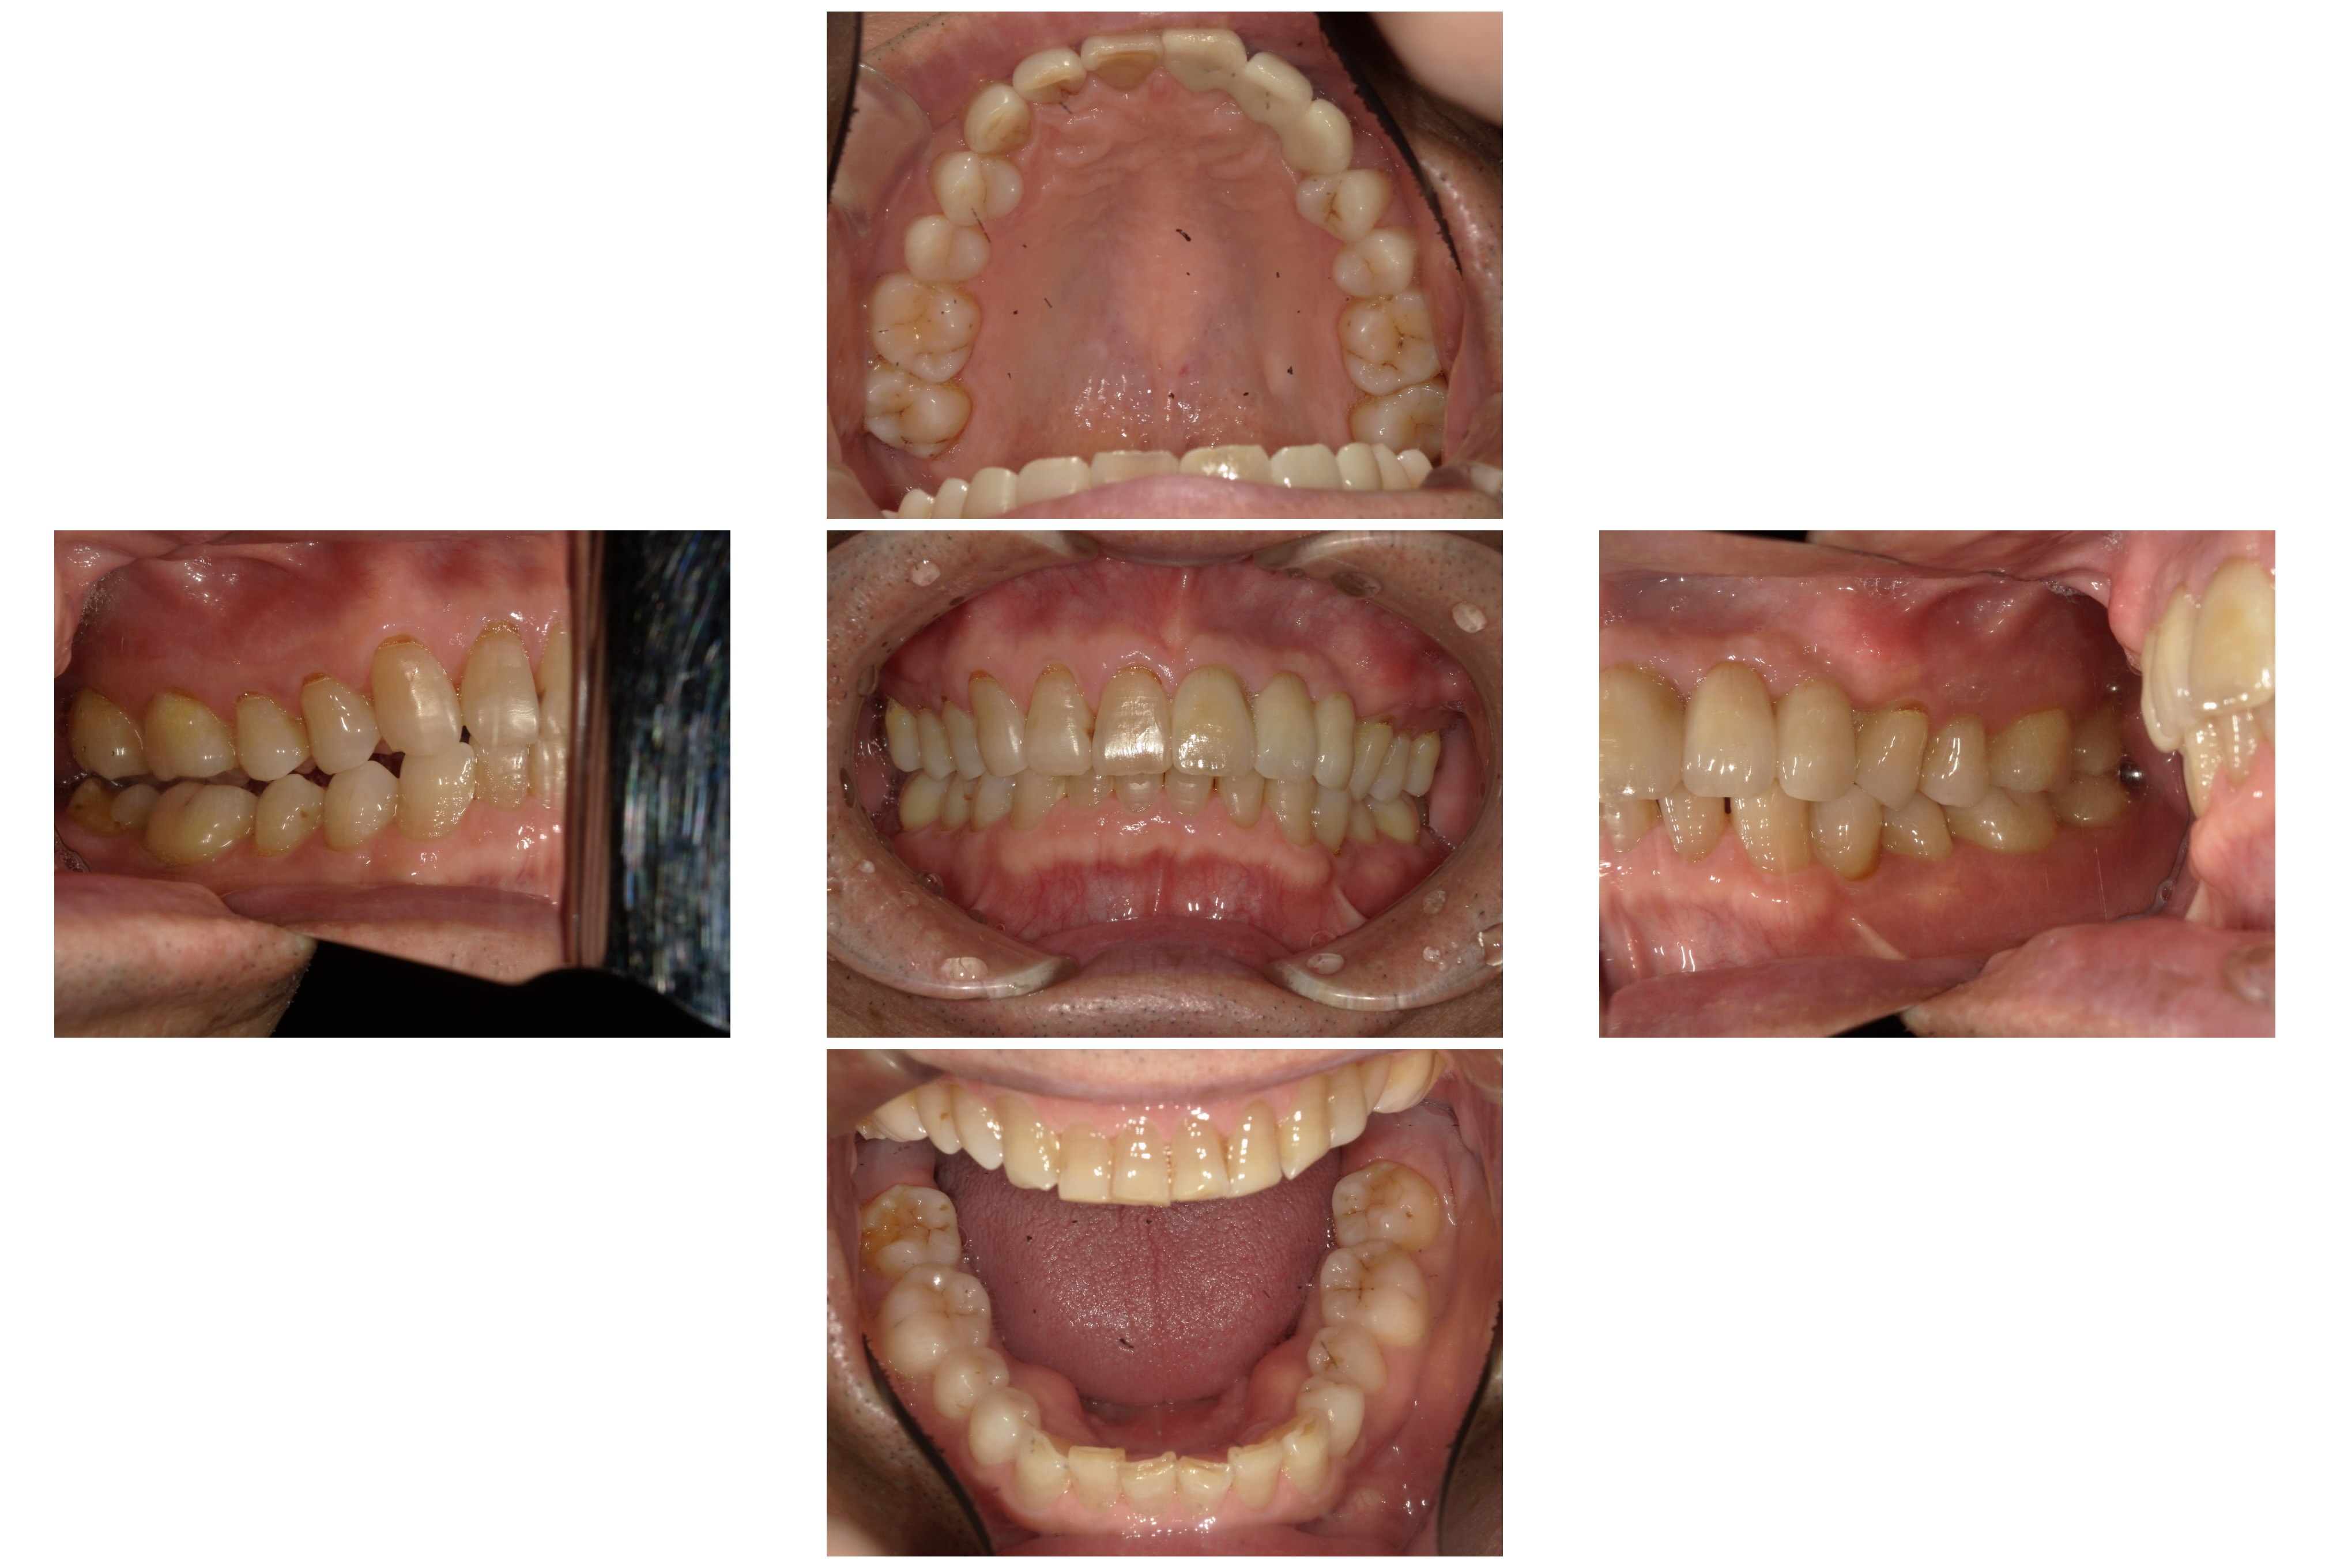

術後